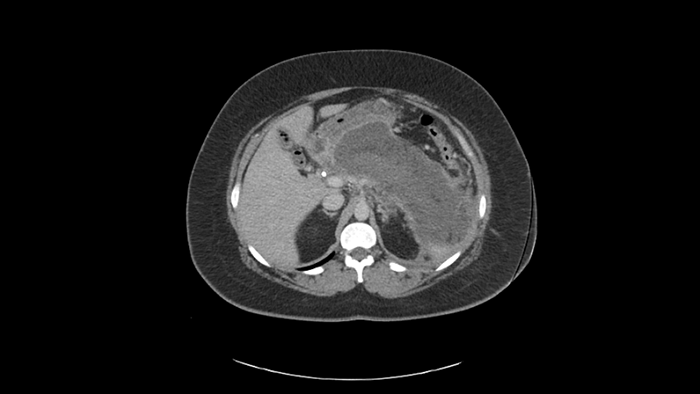

His CT scan results showed:​

• Severe necrotizing pancreatitis​

• Peripancreatic fluid largely replacing the body and tail of the gland​